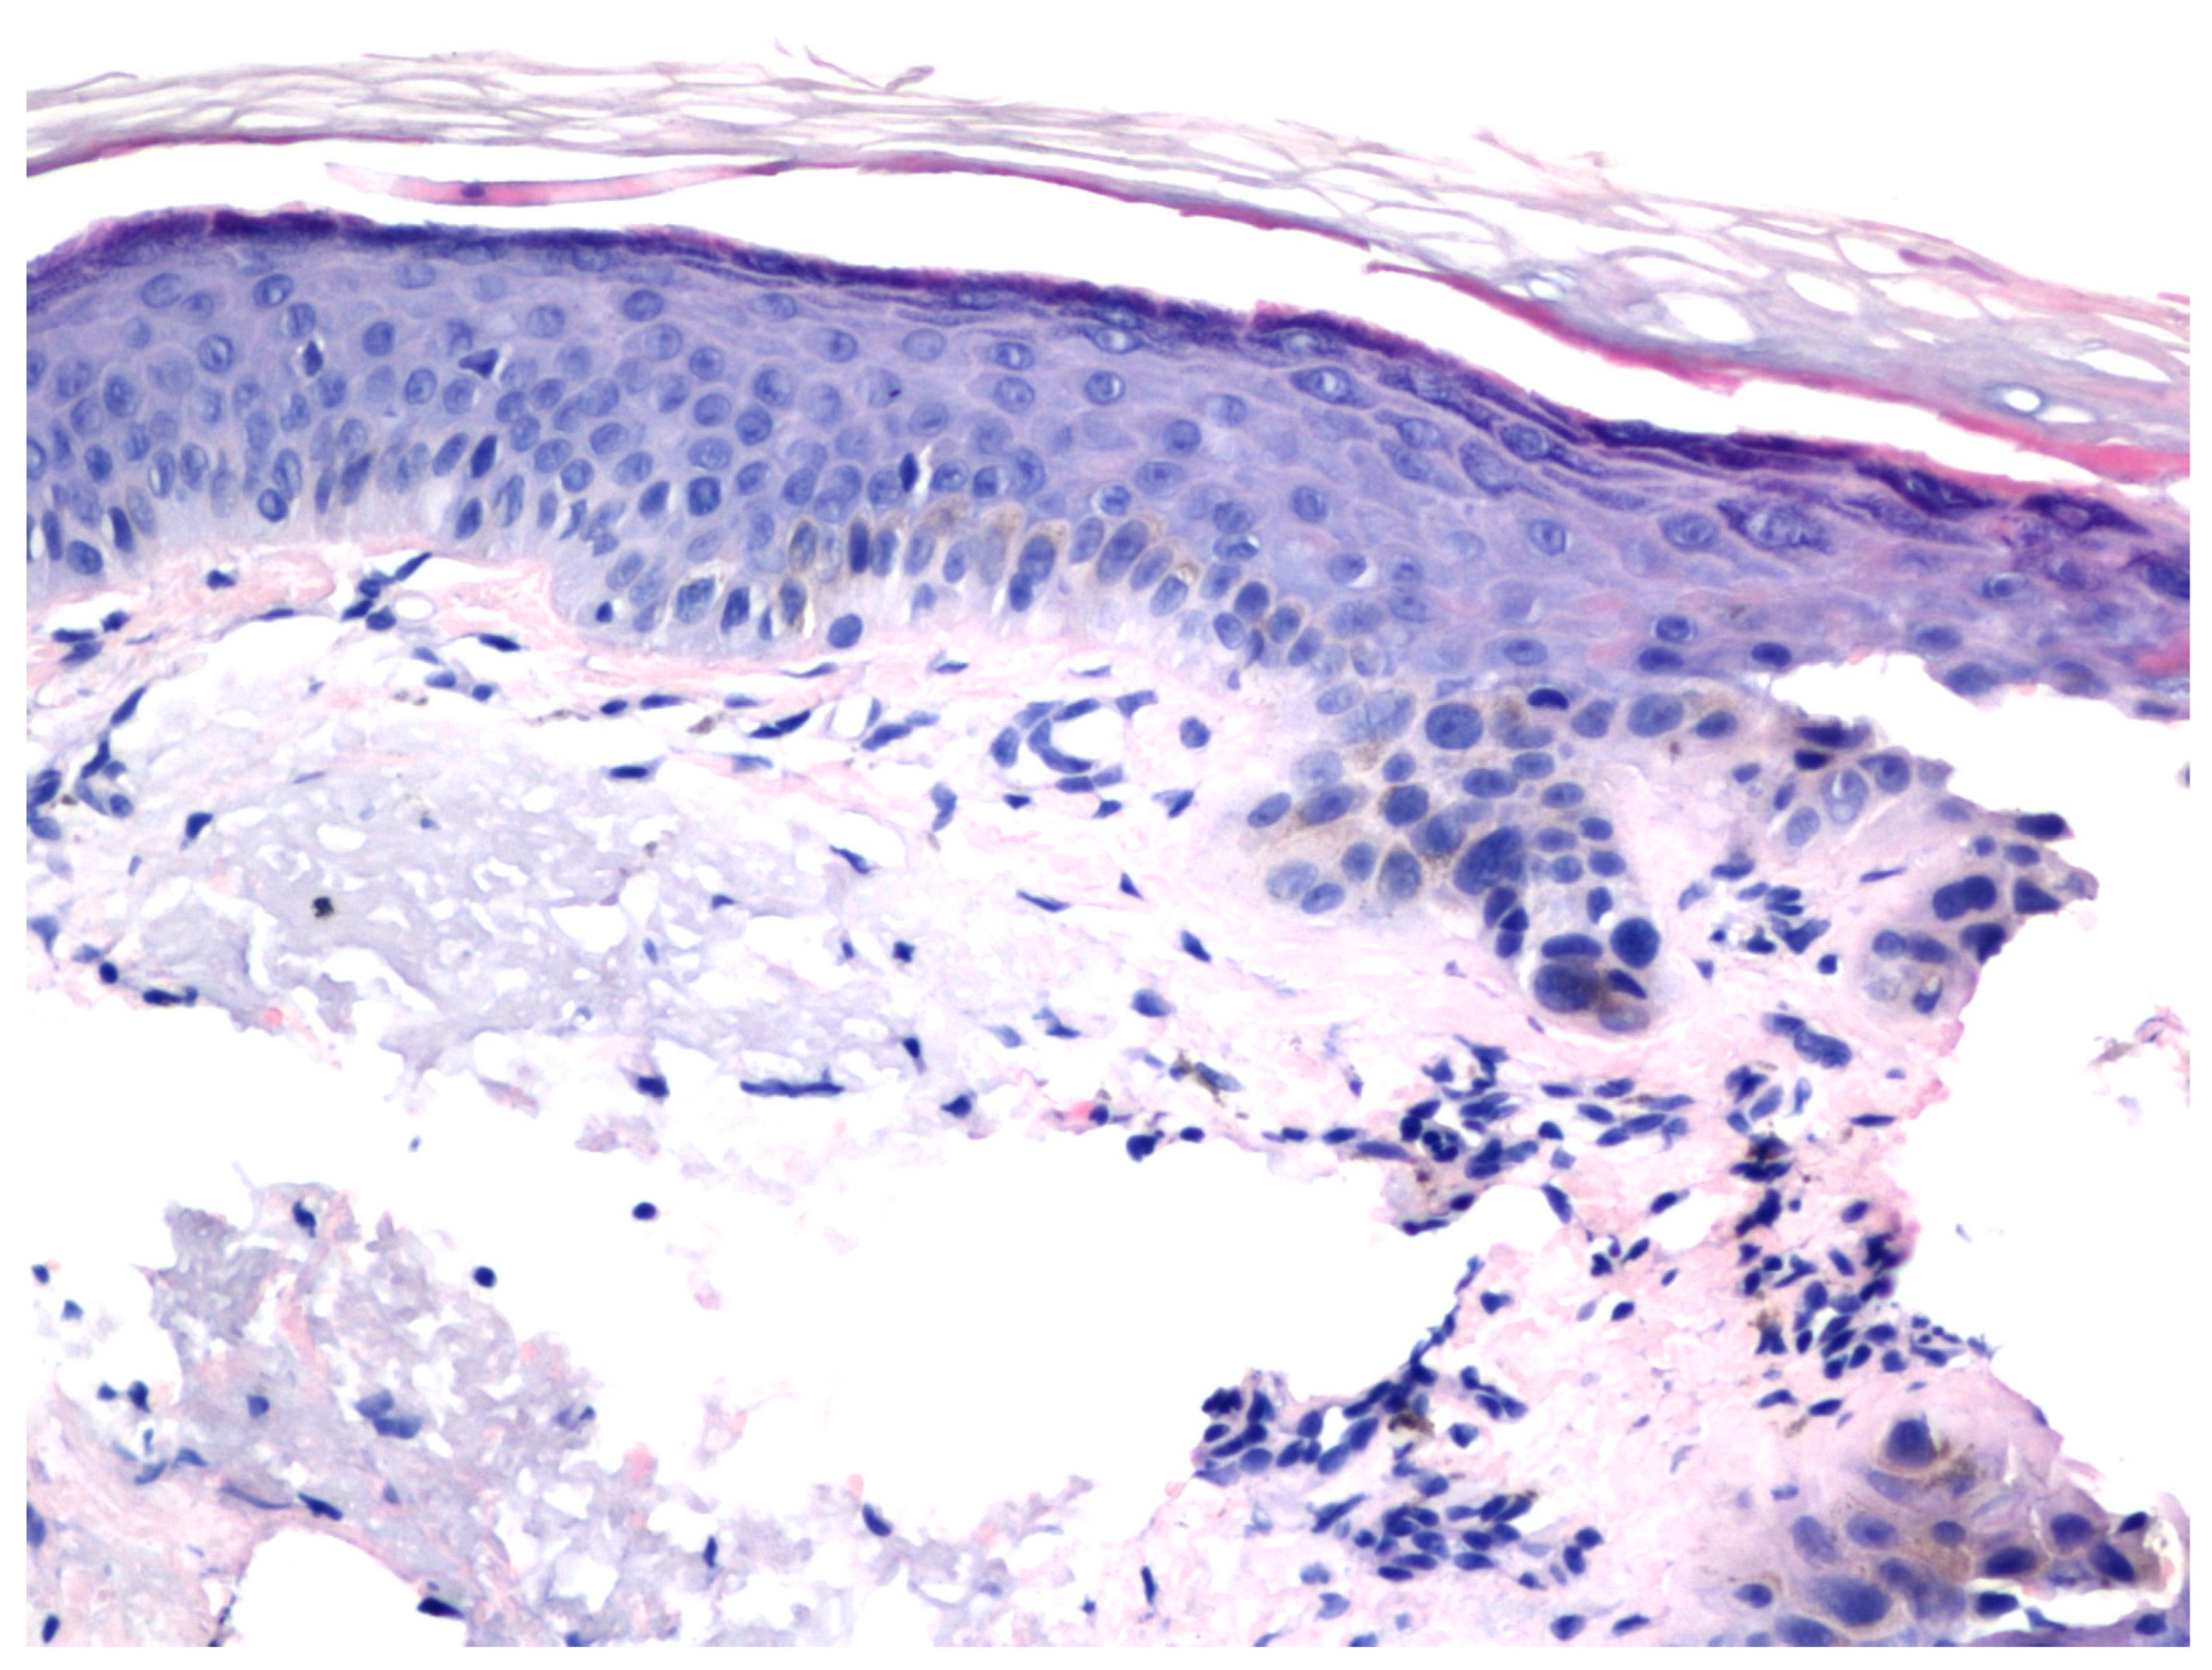

One patient underwent a biopsy of a treatment-resistant lesion. Histopathologic examination revealed residual AK (Figure 3 and Figure 4).

Figure 4. The microscopic examination of the biopsy taken from Figure 3, as seen in haematoxylin and eosin staining, revealed enlarged cells and atypical and hyperchromatic nuclei, indicative of residual actinic keratosis. (H&E: ×200).